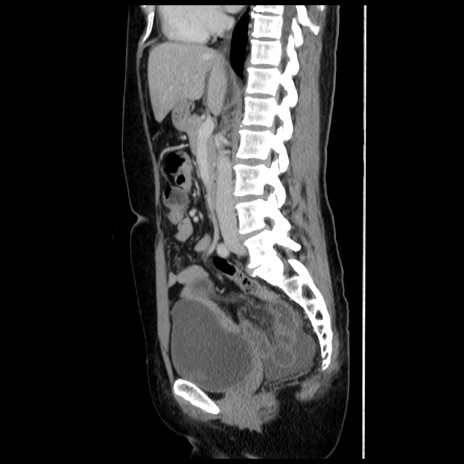

症例10(矢状断像)

【症例】 50歳代女性

【主訴】 腹痛

【現病歴】前日生レバーを食べた。今朝に排便あり。 昼前に突然発症の腹痛を生じ、当院救急外来を受診した。

【既往歴】 子宮筋腫にてで子宮全摘後

【身体所見】 意識清明、腹部:平坦、軟、下腹部やや左を中心に圧痛・反跳痛あり、筋性防御あり

【データ】WBC 7800、CRP 0.07